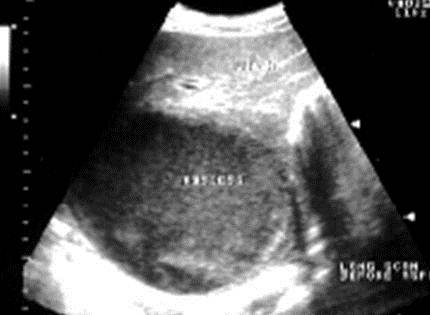

Fatty Infiltration

Fatty infiltration is a benign process that can be reversed with a patients lifestyle change

Common causes are alcoholic abuse, diabetes, and obesity

It occurs from fat accumulation in the hepatocytes which causes damage to these cells

On ultrasound the liver looks hyperechoic and can even be enlarged

The vascular structures may be difficult to visualize because of the increased attenuation